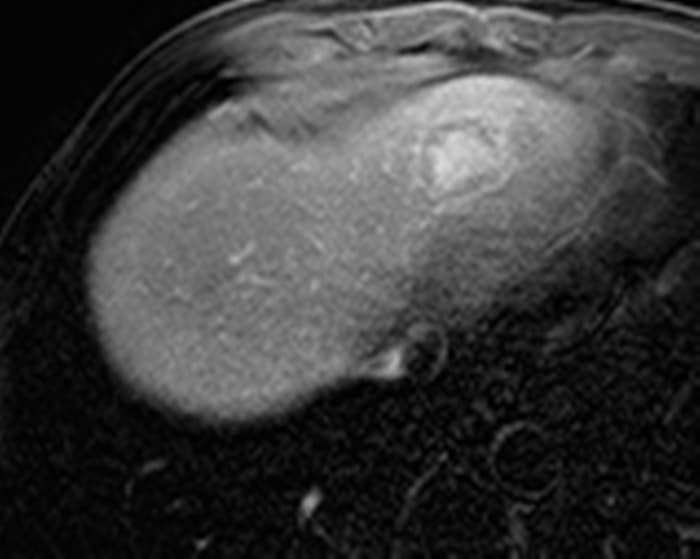

Ung thư đường mật

» Thông tin: Nam giới – 57 tuổi.

» Lâm sàng: Đau bụng.